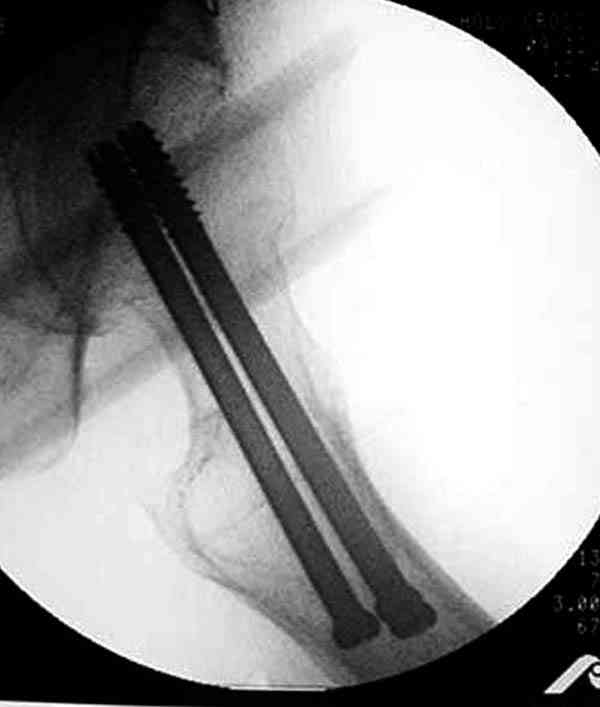

Кстати говоря, ослабление латерального кортекса винтом может способствовать возникновению вертельного и подвертельного перелома.

Коллега Челноков прав, здесь еще имеется риск перелома за счет ослабления латерального кортекса. Во время установки канюлированных шурупов за редким исключением спица вводится с одного раза, множественные попытки ослабляют латеральный кортекс, что станет источником перелома в этом месте.

Здесь случай перелома из-за ослабления латерального кортекса через 3 недели после операции на шейке. Шурупы были установлены под большим углом, слабый латеральный кортекс не выдержал нагрузку.